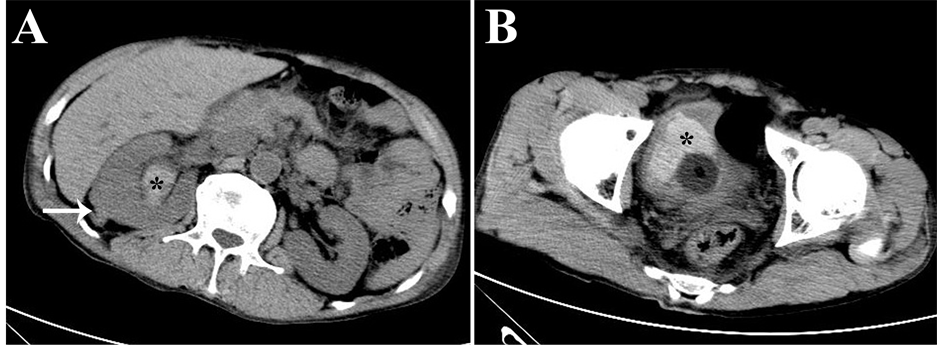

A 51-year male was found having recurrent gross hematuria 12 days after ultrasound-guided percutaneous nep- hrolithotomy (PCNL) due to right renal stone and giant hydronephrosis at other hospital. Recurrent gross hematuria with blood clots were seen after PCNL and these symptoms were slightly relieved through appropriate treatment, such as complete rest in bed, injection hemostasis,red cells transfusion and kidney fistula occlusion. Obvious gross hematuria and blood clots were seen again 2 days after pull out of fistula (one week post-opera- tion) accompany with obstruction of urethral catheter although several bladder irrigation. Because of pain and discomfort within bladder area, the patient was transferred to our hospital for further treatment. Patient felt loss of appetite, poor sleep; weight decreased slightly since the onset, but had any of the following symptoms: fever, joint pain, melena, headache, dizziness, chest tightness, palpitation. Physical examination when hospitalized did not find anything abnormal in his lung, heart and limbs. Body temperature 36.8˚C, pulse 85 beats/min, respiratory 20 beats/min, blood pressure 130/80 mmHg. Blood test: RBC (red blood cell) 2.85 × 1012/L, WBC (white blood cell) 7.17 × 109/L, hemoglobin 91 g/L. BUN (blood urea nitrogen) 7.40 mmol/L, serum creatinine 142.5 μmol/L. The results from all the following tests were normal: bleeding time, blood coagulation time, plasmic electrolytes. CT examination showed the irregular contours of right kidney without hemorrhage around (Figure 1(A)). A lot of blood blots in right renal pelvis, right ureter and bladder (Figure 1(B)).

Figure 1. Abdominal CT images. CT images showed the irregular contours of right kidney (white arrow, (A)), blood blot in right renal pelvis (black asterisk, (A)) and bladder (black asterisk, (B)).